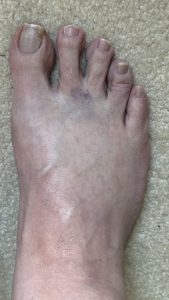

March 14: I took this picture of my swollen foot because I thought it was interesting that I still had the bruise from the injection which I had received just shy of a month prior (February 19). Note the swelling in my foot compared to the previous picture. That is not a happy foot.

March 4: At my follow-up with the podiatrist I told him that my foot was still bruised he said something to the effect of, Sorry for the hematoma (bruise) – may have nicked a vein. It did not hurt, but it looked ugly, and since it seemed like a minor thing none of us were concerned. He couldn’t really do anything for my foot with my back interfering and so now I was at the point with competing doctors who weren’t talking with each other due to being affiliated with different hospitals.